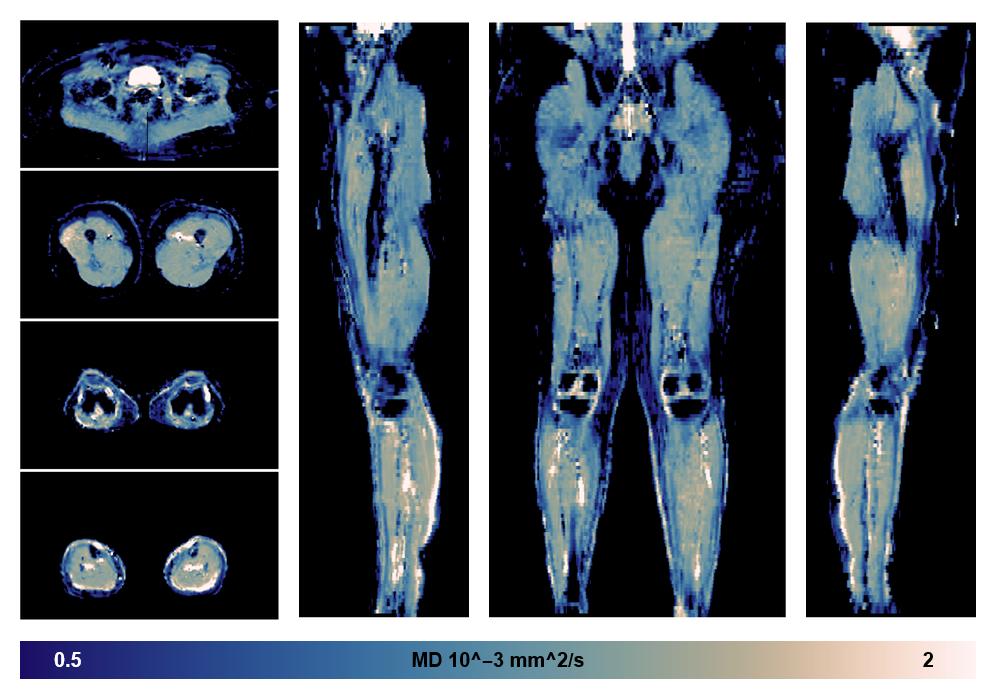

• Mean diffusivity

IVIM corrected whole leg muscle mean diffusivity obtained from diffusion tensor imaging.